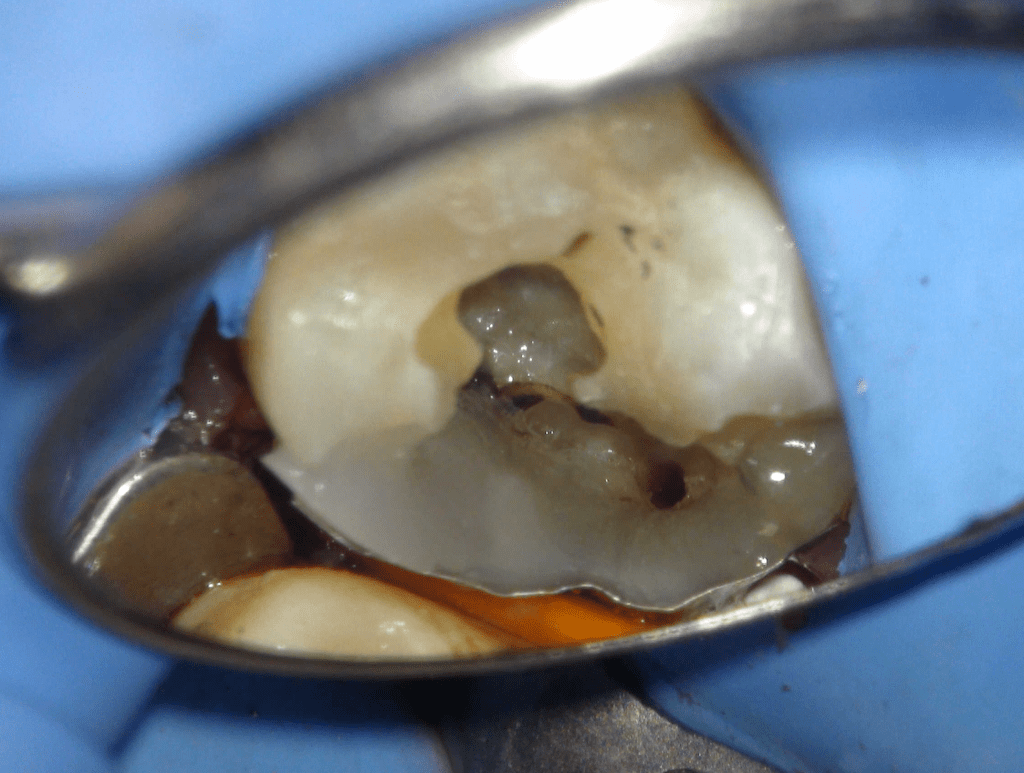

Fisura, remoción amalgama para explorar